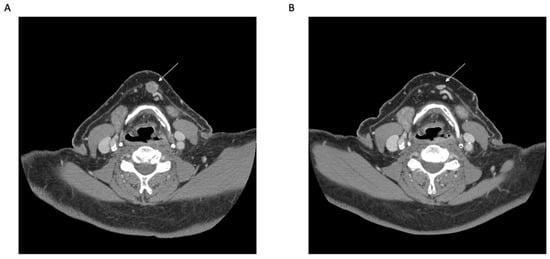

The first systemic therapy to be approved for use in MCC was avelumab, a PD-L1 inhibitor. The long-term data for its use in metastatic MCC as a second-line agent after treatment failure with prior chemotherapy were included in the reporting of the JAVELIN Merkel 200 trial by D’Angelo et al. [24]. They administered 10 mg/kg of the drug IV every two weeks until treatment progression. Of the 88 patients enrolled, ten (11%) achieved a CR and an ORR of 33% was seen. An additional 116 patients were recruited for an investigation of the use of avelumab as a first-line therapy and were later reported by the same group [25]. An ORR of 40% was seen in this cohort. Both groups demonstrated a better response rate in those with PD-L1-positive tumors but found that this was not requisite for its use. Although it is not currently approved for patients with locally advanced disease alone, off-label use in this fashion is being investigated [40,41] (Figure 2).

Figure 2. Neoadjuvant immunotherapy for node-positive Merkel cell carcinoma. Representative axial computed tomography (CT) images before (A) and after (B) neoadjuvant immunotherapy (Avelumab) for recurrent Merkel cell carcinoma metastatic to a left submandibular lymph node (arrow). Histologic interpretation after surgery demonstrated a complete pathologic response.